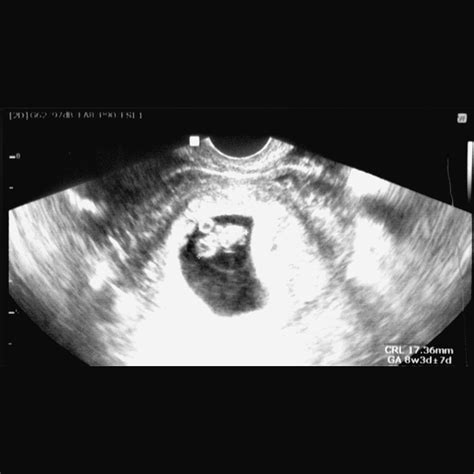

• Determining Gestational Age: Measuring the crown-rump length (CRL) of the fetus helps determine the exact gestational age, which is essential for monitoring the pregnancy’s progress.

Interpreting the Results of an 8 Week Sonogram

The results of an 8 week sonogram are interpreted by a trained ultrasound technician and reviewed by an obstetrician. Key findings include:

• Gestational Age: The CRL measurement helps determine the exact gestational age, which is crucial for monitoring the pregnancy’s progress.